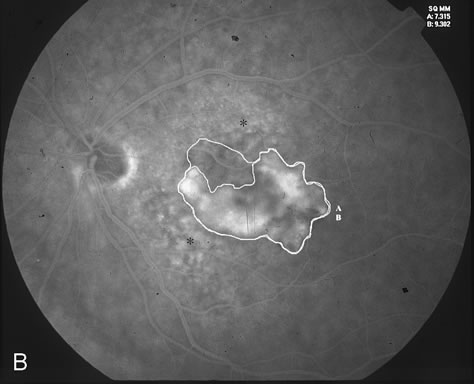

The classic and occult components of CNV are outlined in Figure 2. The percent of the CNV that is classic can then be determined as a proportion of the total CNV. In Figure 2A and B, the area of classic CNV measures 978 square microns and the total lesion measures 11,180 square microns. The classic component is thus 9% of the entire CNV and this lesion is classified as “minimally classic” CNV (defined as less than 50% classic CNV).23,40 The fluorescein angiogram demonstrates another mixed classic and occult CNV lesion in Figure 3. Using digital area measurements, the lesion in Figures 3A and B is composed of 79% classic CNV and fulfils the criteria for predominantly classic, subfoveal CNV that may benefit from verteporfin-PDT based on TAP findings.23,40 The TAP studies also demonstrated a visual benefit in eyes that had prior nonfoveal, thermal laser photocoagulation and subsequent recurrence of CNV below the fovea.23,40 In Figure 4A, subfoveal CNV recurrence in an eye with prior thermal photocoagulation is demonstrated. One month following verteporfin-PDT treatment, Figures 4B (early phase) and 4C (late phase) demonstrate characteristic hypofluorescence of the treated subfoveal CNV on fluorescein angiography.

Fig. 4. A. Mid-phase FA (1:23) demonstrates subfoveal hyperfluorescence corresponding to recurrent CNV (blue arrowhead) adjacent to an area previously treated with thermal photocoagulation (green arrow). B. Early-phase FA (28 seconds) 4 weeks status-post verteporfin-PDT demonstrates hypofluorescence (blue arrowhead) corresponding to the PDT treated area of recurrent CNV. C. Late-phase FA (3:40) 4 weeks status-post verteporfin-PDT demonstrates fluorescein staining in the area of prior thermal laser photocoagulation. There is a small rim of fluorescein staining around an area of hypofluorescence corresponding to the verteporfin-PDT treated area of recurrent CNV (blue arrowhead).